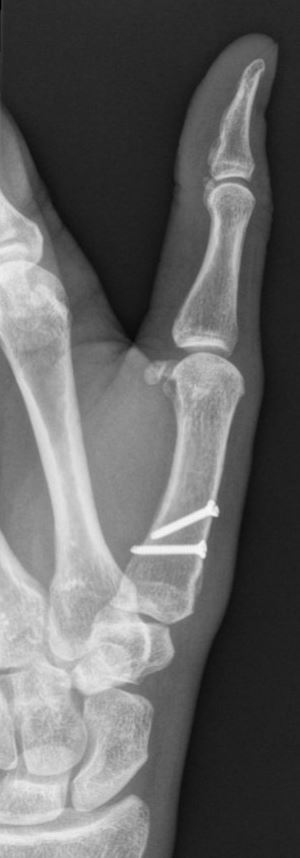

Voor een operatie van de hand of vingers zijn er meerdere opties. Er kan gebruik worden gemaakt van zeer kleine plaatjes en schroeven voor het vastzetten van de breuk. Soms wordt er ook gebruik gemaakt van dunne metalen pennen of van een fixatie aan de buitenkant (zogenaamde ‘externe fixateur’). Welke operatie u uiteindelijk krijgt, is afhankelijk van de eigenschappen van de breuk, de toestand van de huid en de spieren en de voorkeur van uw traumachirurg.